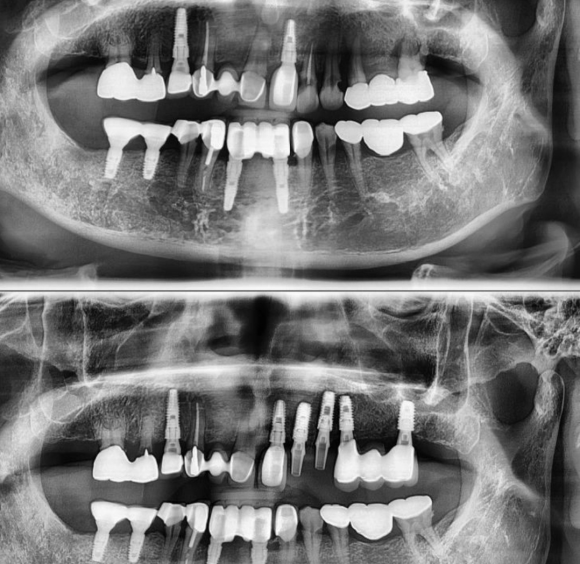

왼쪽위 앞니 심한 부종과 mob로 인한, 발치후 즉시 임플란트 + 즉시 로딩 저희 숭실대 입구역 리더스진 치과는 한달 평균 임플란트 60~100개를 꼼수 없이 가장 좋은 재료와 기술로 원칙적으로 식립하는 치과입니다. #상도동에서임플란트가장많이하는치과

왼쪽위 앞니 심한 부종과 mob로 인한,

발치후 즉시 임플란트 + 즉시 로딩

저희 숭실대 입구역 리더스진 치과는 한달 평균 임플란트 60~100개를 꼼수 없이 가장 좋은 재료와 기술로 원칙적으로 식립하는 치과입니다.